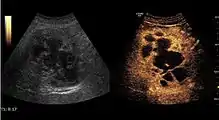

Hemangioma

It is the most common liver tumor with a prevalence of 0.4 – 7.4%. It is generally asymptomatic but also can be associated with pain complaints or cytopenia and/or anemia when it is very bulky. It is unique or paucilocular. It can be associated with other types of benign liver tumors. Characteristic 2D ultrasound appearance is that of a very well defined lesion, with sizes of 2–3 cm or less, showing increased echogenity and, when located in contact with the diaphragm, a "mirror image" phenomenon can be seen. When palpating the liver with the transducer the hemangioma is compressible sending reverberations backwards. Doppler exploration reveals no circulatory signal due to very slow flow speed. CEUS investigation has real diagnosis value due to the typical behavior of progressive CA enhancement of the tumor from the periphery towards the center. The enhancement is slow, during several minutes, depending on the size of hemangioma and on the presence (or absence) of internal thrombosis. During late (sinusoidal) phase, if totally "filled" with CA, hemangioma appears isoechoic to the liver. Deviations from the above described behavior can occur in arterialized hemangiomas or those containing arterio-venous shunts. In these cases, differentiation from a malignant tumor is difficult and requires other imaging procedures, follow up and measurements of the tumor at short time intervals.[4]